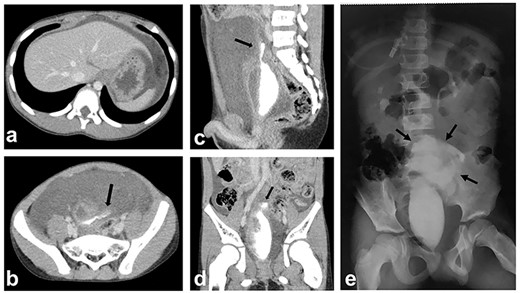

Enhanced abdominal computed tomography (CT) (Fig. 1a–d) and subsequent radiography (Fig. 1e) both revealed a rupture of the urinary bladder. Taken together with the laboratory results, our diagnosis was a bladder rupture without evidence of an underlying pelvic fracture.

Enhanced CT and subsequent radiography; (a, b) enhanced CT shows a massive amount of intraperitoneal free fluid; (b–e) CT cystography and subsequent radiography show contrast material extravasating from the bladder; the contrast is confined to the intraperitoneal space (black arrows: extravasated contrast material).